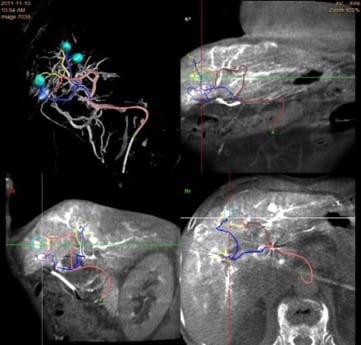

当院では、フィリップス社製3台の血管撮影装置で、各診療科がさまざまな画像下治療(Interventional Radiology:IVR)を行っています。奈良県初となる最新式装置(Philips Clarity)により、高精細な二次元画像に加え、精度の高い三次元画像を作成することで画像下治療に必要な治療手技支援画像を提供しています。

また、従来の装置では抽出困難であった冠動脈ステントや大動脈ステントの形状も明瞭に抽出できる高い画像解像度があり、頭頸部、心臓、腹部、四肢領域の画像下治療に大きな威力を発揮します。さらに最新の画像処理機能によって、従来の被ばく線量に比べ最大80%の被ばく低減を実現させています。

当院ではさまざまな分野の治療に特化した専門性の高い医療従事者からなる多職種チーム医療を推進しており、緊急検査にも積極的に即時対応しています。

主に肝臓癌に対して直接血管内に抗がん剤を投与した後、動脈を塞ぐ物質を注入して血管を塞栓する肝動脈化学塞栓療法(TACE)や肝動脈動注化学療法(TAI)を行っています。また、交通事故や骨盤骨折などの外傷性出血に対する緊急止血術(TAE)も積極的に行っています。

末梢動脈疾患で手足の血管が狭窄・梗塞した場合、バルーンやステントを使用して血管を広げる末梢血管治療(EVT)を行っています。